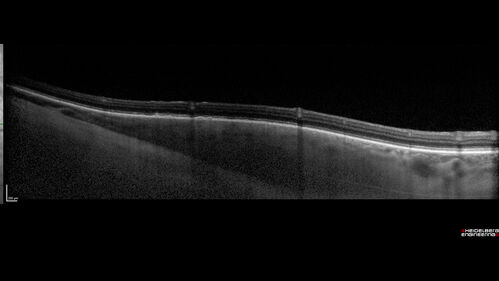

Choroidal Nevus with Halo

Halo Choroidal Nevus